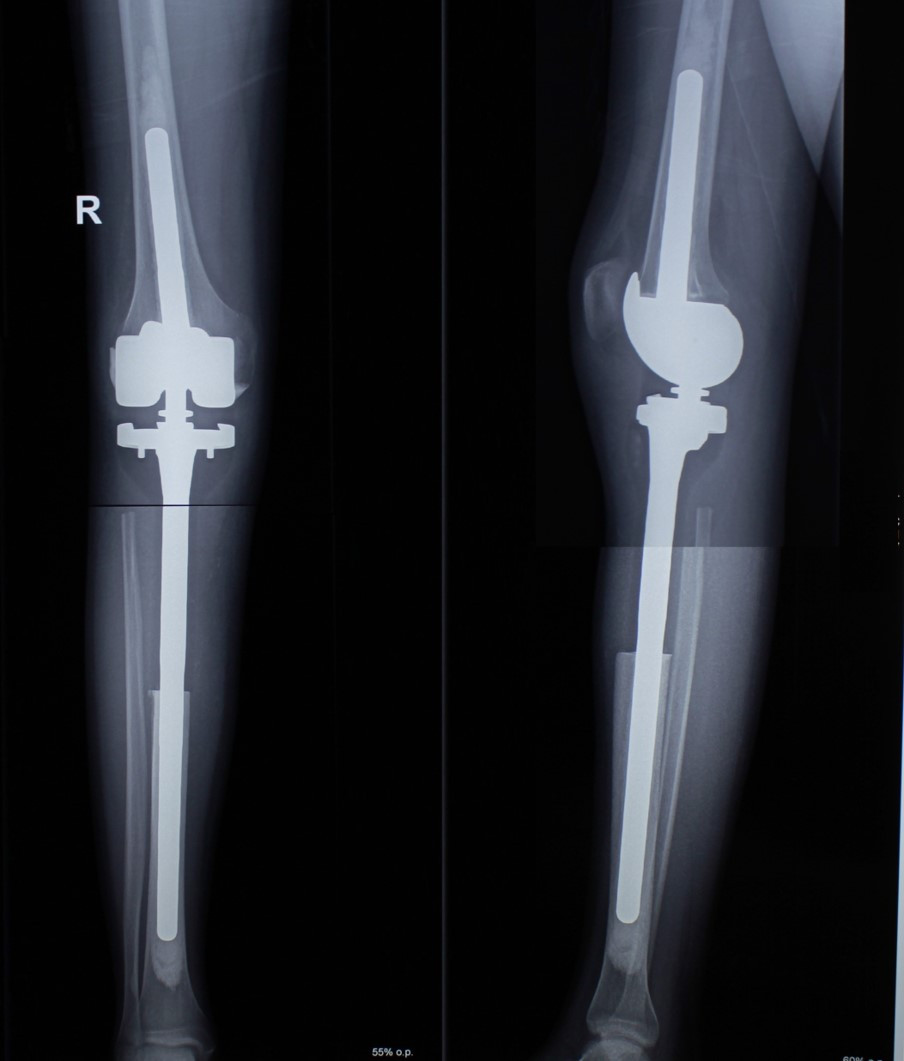

5. Хондросаркома бедренной кости

37-летний пациент обратился в клинику с жалобами на боли в области верхней трети бедра. В ходе обследования была диагностирована хондросаркома бедренной кости. Учитывая, что данный вид опухоли не поддается химиотерапии, специалисты рассмотрели два варианта операции: ампутацию, операцию с сохранением органа. С учетом нечувствительности данного варианта опухоли к лекарственному и лучевому лечению выбор стоял между проведением ампутации (которую рекомендовали в ряде зарубежных клиник в ходе телеконсультаций ввиду выраженного мягкотканного компонента) и органосохраняющим вмешательством. Произведено хирургическое лечение – сегментарная резекция бедренной кости и коленного сустава, замещение дефекта индивидуальным эндопротезом. Спустя 7 лет после операции пациент жив, местного рецидива и отдаленных метастазов заболевания не выявлено, функция оперированной конечности оценивается на «отлично».

До операции

После операции